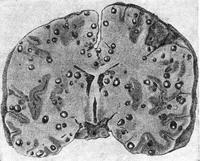

![]() Рис. 2. Цистицеркоз головного мозку людини. |

Зараження людини цистицеркозом відбувається при проковтуванні зародків (онкосфер) свинячого ціп'яка з харчовими продуктами, забрудненими фекаліями інвазовану свинячим цепнем людини. Цистицеркоз може бути ускладненням кишкового тениоза, при якому зрілі членики гельмінта закидаються в шлунок під час антиперистальтики кишечника. У шлунку членики перетравлюються, і з матки звільняються яйця паразита з онкосфера. Цистицерки локалізуються в різних органах людини; частіше їх виявляють в головному і спинному мозку, ока, іноді в шкірі, м'язах та інших тканинах (рис. 2).